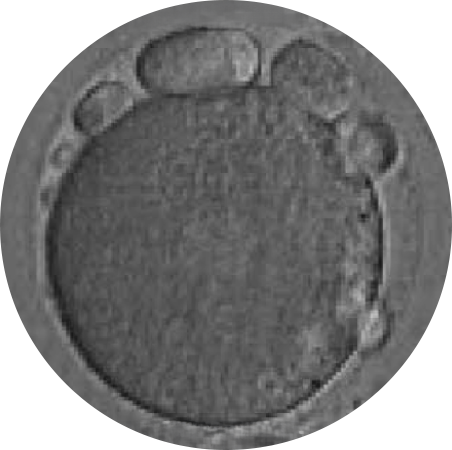

- Embryo Culture in Magnetic Fields: Embryos develop in a specialized magnetic environment that:

- Reorganizes the cytoskeleton

- Optimizes mitochondrial distribution

- Activates essential ion channels

- Reduces unnecessary energy expenditure

By using the patient’s mitochondria to revitalize the eggs and employing magnetic fields in embryonic culture, they facilitated proper cell division, significantly increasing the chances of obtaining viable embryos. This combination of metabolic diagnosis, egg revitalization, and magnetic fields has set a new precedent in assisted reproduction.